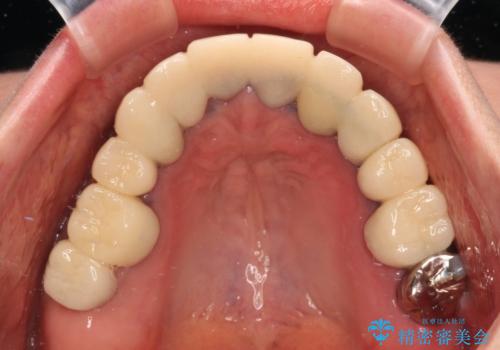

- 近医にて古いかぶせ物をセラミッククラウンにしようと治療を開始したものの、仮歯での咬み合わせが不安定とのことで、転院を希望して来院された患者様です。

骨格的に下顎骨が前方位に位置しており、上下前歯部の先端同士が接触する切端咬合でした。

このような方は咬み合わせが大きく変わると不安定となるため、まずは装着されている仮歯で咬合調整を行い、安定した咬み合わせとした後に、新しい仮歯に置き換え、その後オールセラミッククラウンにて補綴治療を行うこととしました。

仮歯で咬み合わせの調整を行ってからは、特に不安定になることもなく、非常にスムーズに治療を進めて行くことができました。

前歯奥歯ともに望ましくない力がかかりやすい咬み合わせであるため、就寝時にはマウスピースを使用するようにお伝えしております。